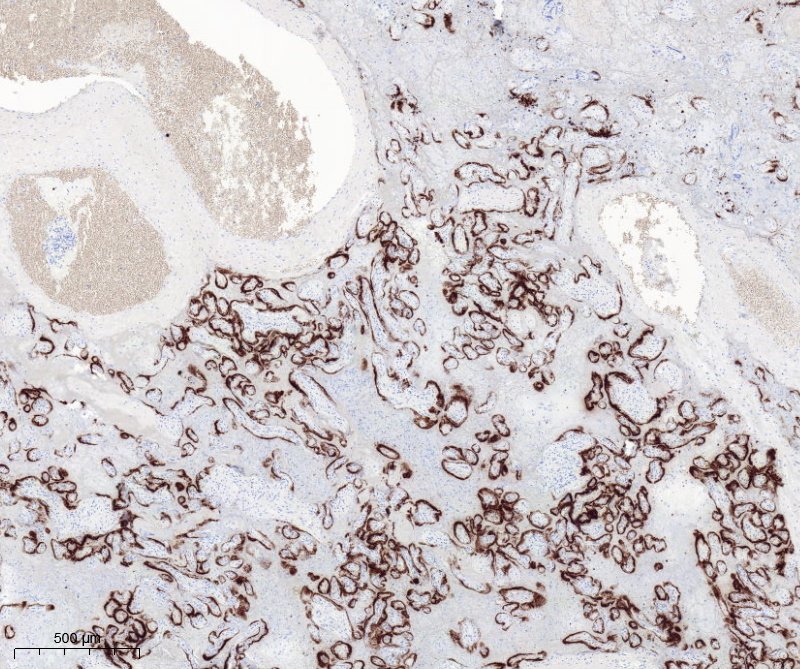

📣 El Grup de Treball de #PediPath de l'SCAP ha demostrat que la #Covid_19 pot danyar massivament la #placenta i produïr la mort fetal: el Dany Trofoblàstic Difùs es la lesió histològica característica. 🗒️Garrido-Pontnou et al. Modern Pathology. Volume 34, (2021)

Researchers from #VallHebron, @hospitalclinic - @idibaps and @parctauli show that #covid can damage the placenta of pregnant women. This damage is very rare and lead to abnormal blood flow between mothers and fetuses. Published in @ModernPathology. More: https://t.co/VVt3iEuVZF

L'extensió de la lesió en una #placenta infectada per #coronavirus es decisiva en el pronòstic fetal. #pedipath #placentapath @vallhebronpath @AutopsiaFetal

El @diariARA explica l'estudi que mostra que la #covid pot infectar la placenta en gestants. La Dra. @martiponi, del Servei d'Anatomia Patològica #VallHebron, explica que l’extensió de la lesió i el temps des que la gestant es va contagiar són decisius. https://t.co/23orkq4BzU